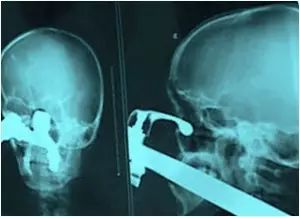

6.这是2008年一宗谋杀案,尸体被发现在公寓被子弹击中头部。透视检查过后发现,他是被射钉枪打死的

这是2008年一宗谋杀案,尸体被发现在公寓被子弹击中头部。透视检查过后发现,他是被射钉枪打死的